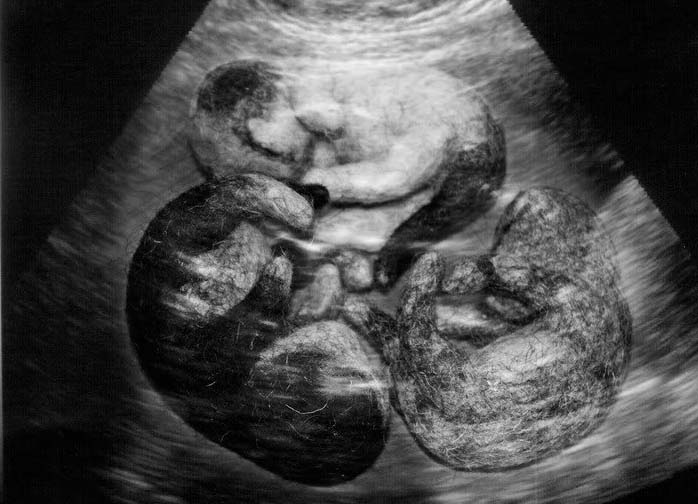

УЗИ

Важно! УЗИ на данном этапе показывает биение сердца порядка 230 уд./мин.

Плановые УЗИ при беременности

Специалист может назначить УЗИ почти в любой момент беременности, если состояние животного вызывает сомнения. На ранних сроках владелец может обратиться к ветеринару, чтобы подтвердить или опровергнуть наличие беременности.

Дальше отслеживается развитие плода, устанавливается количество будущих котят. В любом случае посещение ветеринарной клиники рекомендовано как в профилактических целях, так и при возникновении ощущений тревоги за состояние своего любимца.

Плановое УЗИ